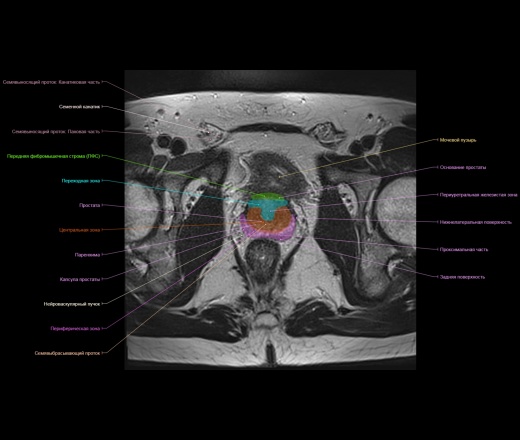

Представленный материал носит обучающий характер, не стал размещать в разделе Презентации, из за отсутствия вьюера с возможностью именно прокручивать изображения как на рабочей станции.

https://www.imaios.com/ru/e-Anatomy/Grudnaya-kletka-bryushnaya-polost-taz/Muzhskoj-taz-MRT

https://radiopaedia.org/cases/normal-prostate-mri

http://event.medradiology.moscow/d/1387577/d/mrt_predstatelnoy_zhelezy.pdf

Надписи очень плохо видно, разместил в разделе Презентации там видно получше.